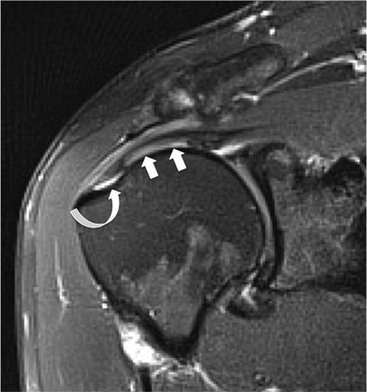

The primary sign of a rotator cuff FTT is a focal deficiency of the tendon (Figs. 46-4 and 46-5). This nearly always occurs at the tendon insertion on the tuberosity. The margins of the tear are best delineated when there is fluid within the tendon defect. Secondary signs of an FTT include the presence of fluid in both the GHJ and SAB, and flattening or concavity of the subacromial fat plane.

PTTs are less reliably demonstrated by both MRI and US, and it may be difficult to differentiate tendinopathy from partial tears. Focal clefts, tears, or tendon thinning affecting the articular margin of the footprint of the tuberosity are most common (Figs. 46-6 and 46-7). Tendon thickening is not always present. It is important not to mistake magic angle phenomenon on short TE MR sequences or anisotropy on US as evidence of tendinopathy.2